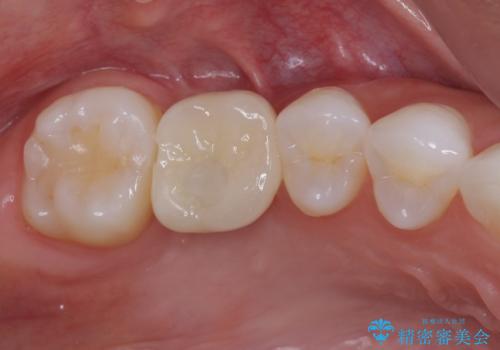

セラミックインレーを装着したことで、とても自然な仕上がりとなりました。

患者様も大きく口を開けても気にならなくなった、大変喜んでくださいました。